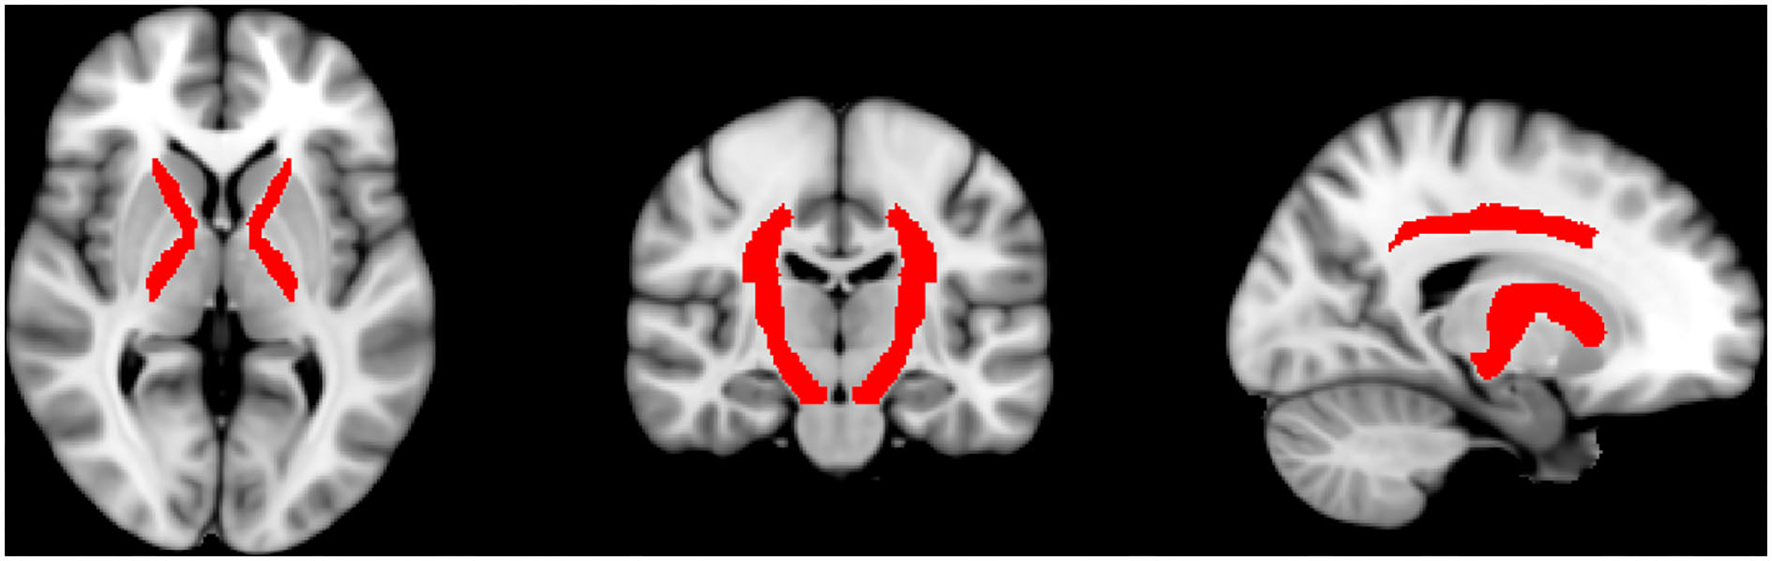

Supplementary to that, we evaluated multiple regions of interest (ROIs) covering areas with special relevance to the somatosensory system and regions with high-significant regions and wide clusters. For this, we used the JHU ICBM DTI-81WM-Labels Atlas, which can be freely downloaded and used within the FSL software package (http://www.loni.usc.edu/ICBM/Downloads/Downloads_DTI-81.shtml) (14). The regions that should be included were selected manually and subsequently, the exact size of the ROIs was automatically defined on the co-registered brains according to the defined size of the regions of the atlas. The ROIs corresponding to somatosensory regions included the anterior limb of the internal capsule (ALIC), posterior limb of the internal capsule (PLIC), corona radiata superior (CRS), and posterior (CRP) and the cerebral peduncles. Further ROIs were the body, genu, and splenium of the corpus callosum, post-thalamic radiation (includes optic radiation), and superior longitudinal fasciculus. A graphic representation of the sensory ROIs is shown in Figure 1. By using the above-drawn masks, the significant (p ≤ 0.05) FA and RD values for each subject were extracted by using fslmaths and flsmeants. Then, FA, RD, and SSEPs were correlated by using Spearman correlation with a correction for multiple comparisons to prevent type 1 error by using Bonferroni correction. Prism 9 Software (Graphpad, San Diego, CA, USA) was used to perform these correlations. Classification of correlation coefficient rho is low (0.0–0.2), moderate (0.2–0.5), high (0.5–0.8), and perfect (0.8-1.0).

Figure 1

Shown are the automatically drawn ROIs that correspond to sensory tracts by using the DTI-81 Atlas in the FMRIB library package.